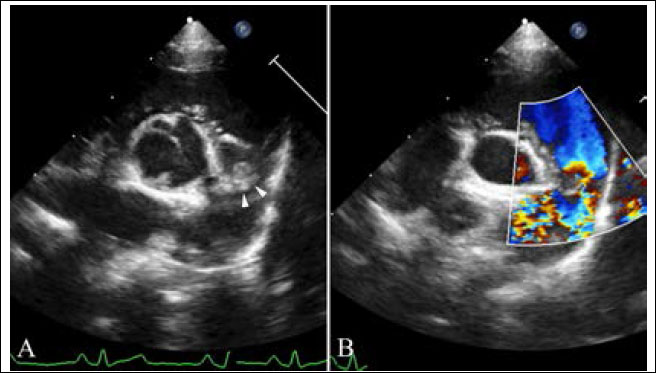

Transthoracic echocardiography (Affiniti 50; Philips Medical Systems, WA, USA) was performed with a sector-array transducer (4–12 MHz). An abnormal slit-like tunnel structure, 2.2 mm in internal diameter, connecting the ascending aorta to the left ventricle was detected above the sinutubular junction. The opening of this structure was located in the base of the ventriculoaortic junction between the anterior mitral leaflet and non-coronary cusp. The morphology and motion of both the mitral and arterial valves were normal, with no evidence of aortic stenosis, mitral regurgitation, or valvular vegetation (Supplementary video I). During the diastolic phase, a regurgitant jet was detected along the aortic cusps with a 2.8 m/second peak velocity and 32 mmHg pressure gradient and along the anterior mitral leaflet with a 2.3 m/second peak velocity and 22 mmHg pressure gradient from the tunnel opening to the left ventricle (Fig. 2, Supplementary Video I). There was mild left ventricular eccentric hypertrophy with an internal diameter in diastole and systole of 23.7 mm (reference range: 16.70–18.93 mm) and 12.2 mm (reference range: 9.04–10.98 mm), respectively. The normalized value of the end diastolic left ventricular interior dimension was 1.63 (reference range: <1.7). The interventricular septum thickness in diastole and systole was 4.9 mm (reference range: 5.70–7.53 mm) and 6.1 mm (reference range: 8.60–10.64 mm), respectively. The thickness of the left posterior wall during diastole and systole was 4.6 mm (reference range: 4.53–6.03 mm) and 7.0 mm (reference range: 7.97–9.55 mm), respectively. Left ventricular systolic function was normal based on fractional shortening of 48.5% and an ejection fraction of 61.6% obtained by Simpson’s method of discs.

Fig. 2. Echocardiography of right parasternal five chamber view (A–C), oblique right parasternal short axis view of the heart base (D), and oblique left apical long axis view (E,F). (A, B) an abnormal slit-like tunnel structure (arrowheads) next to the aorta is shown. (A,C) The opening of this tunnel structure is located in the base of the ventriculoaortic junction between the non-coronary cusps and anterior mitral leaflet. (D–F) during the diastolic phase, a regurgitant jet is detected along the aortic cusps (black arrows; 2.8 m/second peak velocity, 32 mmHg pressure gradient) and along the anterior mitral leaflet (white arrows; 2.3 m/second peak velocity, 22 mmHg pressure gradient) from the tunnel opening to the left ventricle.

In the main pulmonary artery, there was abnormal discrete tissue approximately 7.0 mm away from the pulmonary valve, consistent with a supravalvular stenotic lesion. Color flow and continuous-wave Doppler showed turbulent blood flow originating at the level of the stenotic lesion with a 3.8 m/second peak velocity (57 mmHg pressure gradient). No marked post-stenotic dilation of the main pulmonary artery was observed (Fig. 3, Supplementary Video II). The right atrium and ventricle were normal in size and appearance.

Fig. 3. Echocardiography of right parasternal short axis view showing the right ventricular outflow tract. (A) The supravalvular lesion (arrowheads) is shown distal to the pulmonary valve. (B) color flow Doppler ultrasound shows turbulent blood flow originating at the level of the supravalvular stenotic lesion.